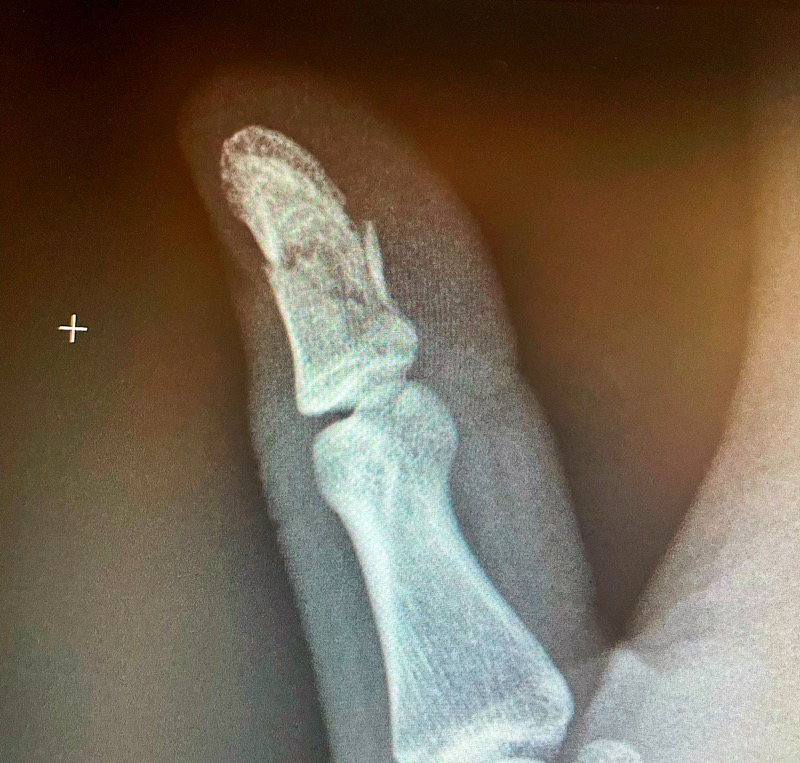

I’m not a doctor

But, I think I see the problem in Sam's X-ray.

Sam fractured his thumb this morning. Fortunately the fracture is just the tip of the thumb, so no joint or ligament damage. It does mean no golf and video games will be tough to play for the next 4-6 weeks. He says it hurts a bit but he will be fine.